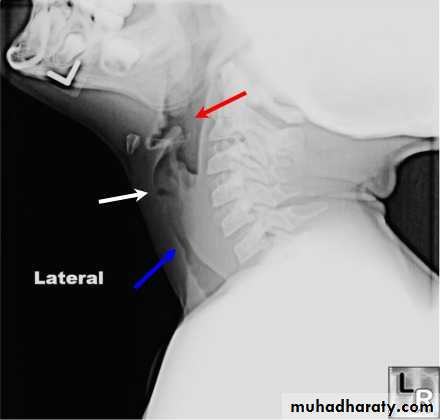

Lateral X-ray of the neck, which shows increase in prevertebral soft tissue shadow or an air-fluid level.

Retropharyngeal space

Acute retropharyngeal abscess

Retropharyngeal abscess

Lateral X-ray of the neck shows evidence of bone destruction and loss of the normal curvature of the cervical spine.